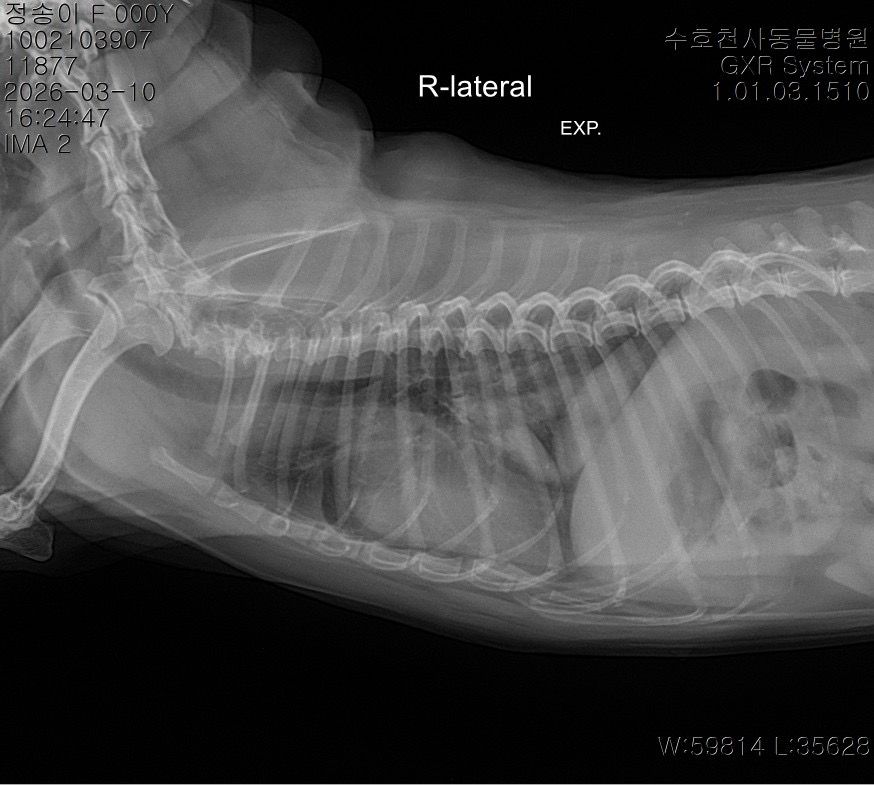

말씀주신 것처럼 보여주신 방사선에서 흉강 내 종양 (폐, 흉강 등)이 의심되는 상황입니다. 다만 방사선 사진만으로는 종양 여부와 정확한 위치, 개수, 성격을 완전히 판단하기 어렵고 CT 촬영을 통해 정확한 판단이 이루어져야 수술 여부 등을 결정할 수 있습니다. 좌측 폐는 앞엽과 뒷엽으로 나눠지긴 하고, 사진 상으로는 좌측 뒷엽 혹은 오른쪽 폐와 왼쪽 폐 사이에 있는 덧엽 부분에도 종괴가 위치하는 것으로 보이지만, 방사선으로는 어느 폐엽에서 발생한 것인지 정확히 구분할 수는 없습니다.

종괴가 단일 병변인지 여러 개인지, 정확히 어느 폐엽에서 시작되었는지, 주변 조직이나 다른 폐엽으로 이어져 있는지,

원발성 종양인지 전이성 병변인지 등을 알려면 CT 촬영이 필요하며 치료 방향도 CT 결과에 따라 달라집니다. 만약 한 두개의 폐엽에 국한된 단일 종괴라면 경우에 따라 해당 폐엽을 제거하는 수술을 고려하는 경우가 있습니다. 하지만 주변 조직으로의 침습, 원격전이 혹은 너무 많은 엽을 포함하고 있어 수술 후 호흡 합병증이 예상되는 경우 수술로 완치 기대는 어렵습니다. 빠른 CT 촬영을 추천드립니다.

사진상으로는 상당히 전형적인 원발성 폐종양의 방사선 양상이지만 말씀 하신 "방사선 엑스레이 촬영 한 것을 통해서서도

폐 종양인지 아닌지, 갯수를 확인가능한지

한 폐엽에만 있는 상황인건지 아니면 윗쪽 중간 폐엽과도 이어져있는지 원발성,악성 등등"에 해당하는 내용은 방사선 사진으로 평가하는게 아닌 흉부 CT검사로 확인해야 하는 사항들입니다. 흉부 방사선 검사는 저렴하지만 정확도와 세밀한 내용 평가에 제한이 있습니다. 우선 주치의와 상의하시고 흉부 CT검사를 촬영 한 후에 침습이나 전이 여부 평가하고 수술 계획 잡으시기 바랍니다. 원발성 폐종양인 경우 악성이더라도 수술로도 완치가 가능한 몇 안되는 질환이니 수술을 빨리 하면 할 수록 좋을 수 있으니 아이에게 주워진 시간을 아끼시기 바랍니다.